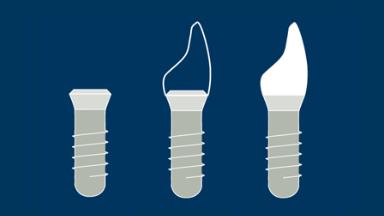

- list the definitions of immediate, early and conventional implant loading protocols